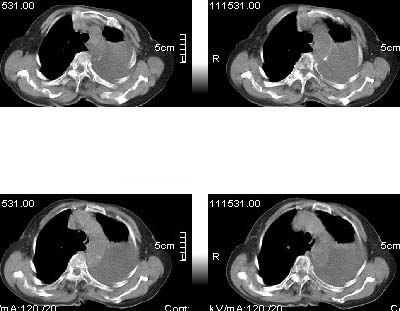

标题: CT4907:[原创]胸部平扫,请讨论!谢谢!!

考虑:左侧大量胸腔积液伴下叶压迫性且不张。

中央型肺癌,下叶不张,胸水

左侧大量胸腔积液伴下叶压迫性且不张,心包积液,左下叶支气管变窄,建议增强扫描,排除占位

左侧大量胸腔积液伴左下肺不张,左侧支气管狭窄,左舌段有膨胀感,中央型肺癌待排,心包有少量液体。肝顶部低密度影,需进一步检查

左侧大量胸腔积液伴左下肺不张,左侧支气管狭窄,左舌段有膨胀感,中央型肺癌待排,心包有少量液体

左侧大量胸腔积液,左下叶受压不张,纵隔向右侧轻移位,虽未见明显骨质破坏,但临床有刺激性咳嗽、胸疼等都支持非善类病变,应穿刺抽液细胞学检查,考虑右肺癌并胸膜转移。肝顶部似有低密度影,可进一步检查,排除转移灶。

患者以抽胸水到上级医院作细胞学检查,肝右顶部的确是{患者以作b超:囊性低密度区,考虑囊肿?}病灶。我的初步意见是考虑是左侧中央型肺癌。

1、高度怀疑:左肺中央型肺癌伴肺不张、胸水;

2、肝上病灶暂考虑囊肿。

3、心包内脂肪影清晰,未见积液。

左侧大量胸腔积液伴左下肺不张,左侧支气管狭窄,左舌段有膨胀感,中央型肺癌待排.